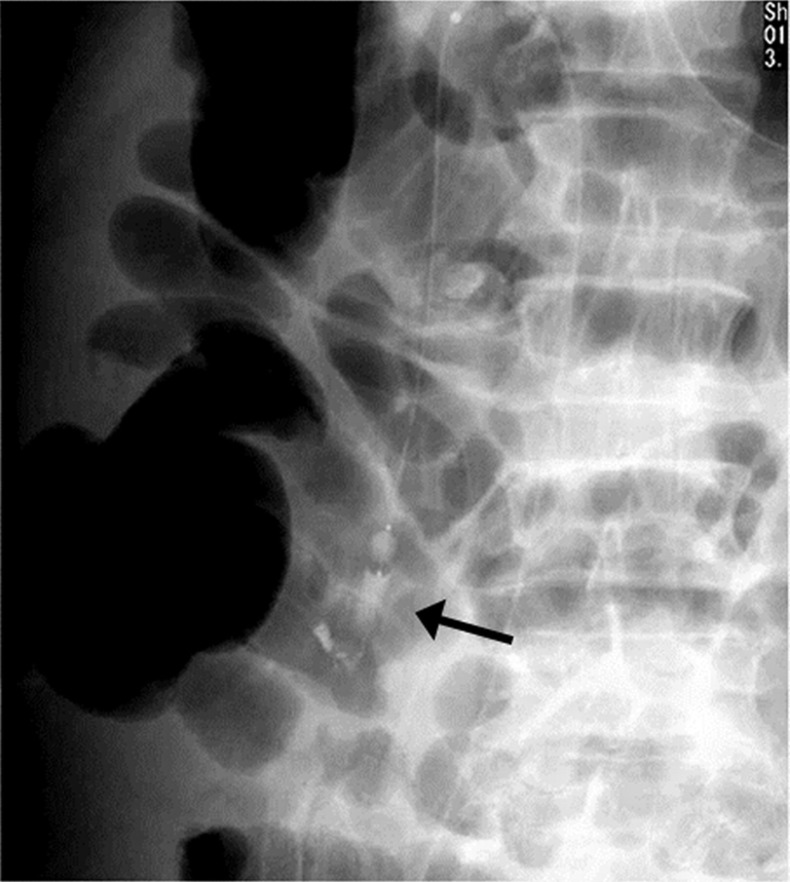

十二指肠静脉曲张是异位门静脉系统分流,不容易导致胃肠道出血。球囊闭塞逆行经静脉闭塞术是治疗胃静脉曲张的常用方法。我们报告一位60岁男性患者,由于起源于胰十二指肠下静脉的十二指肠静脉曲张破裂而导致黑黑;引流到性腺静脉。他的十二指肠静脉曲张破裂成功治疗双球囊闭塞栓塞治疗。

Duodenal varices are ectopic portosystemic shunts that do not tend to result in gastrointestinal bleeding. Balloon-occluded retrograde transvenous obliteration is an established treatment for gastric varices. We report a 60-year-old man with melena due to ruptured duodenal varices originating at an inferior pancreaticoduodenal vein; drainage was into a gonadal vein. His ruptured duodenal varices were successfully treated by dual balloon-occluded embolotherapy.